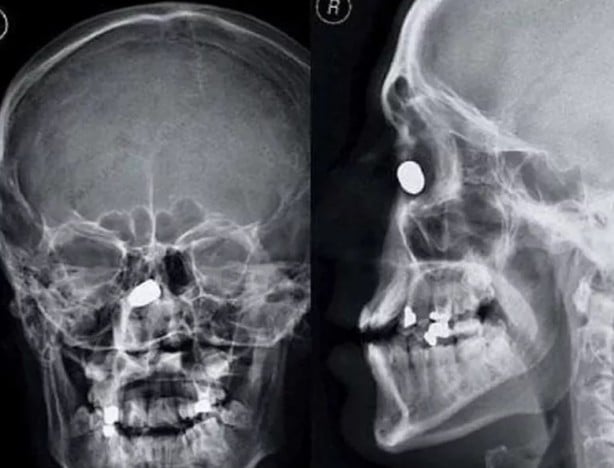

İşte görenleri şaşırtan o röntgen filmleri...